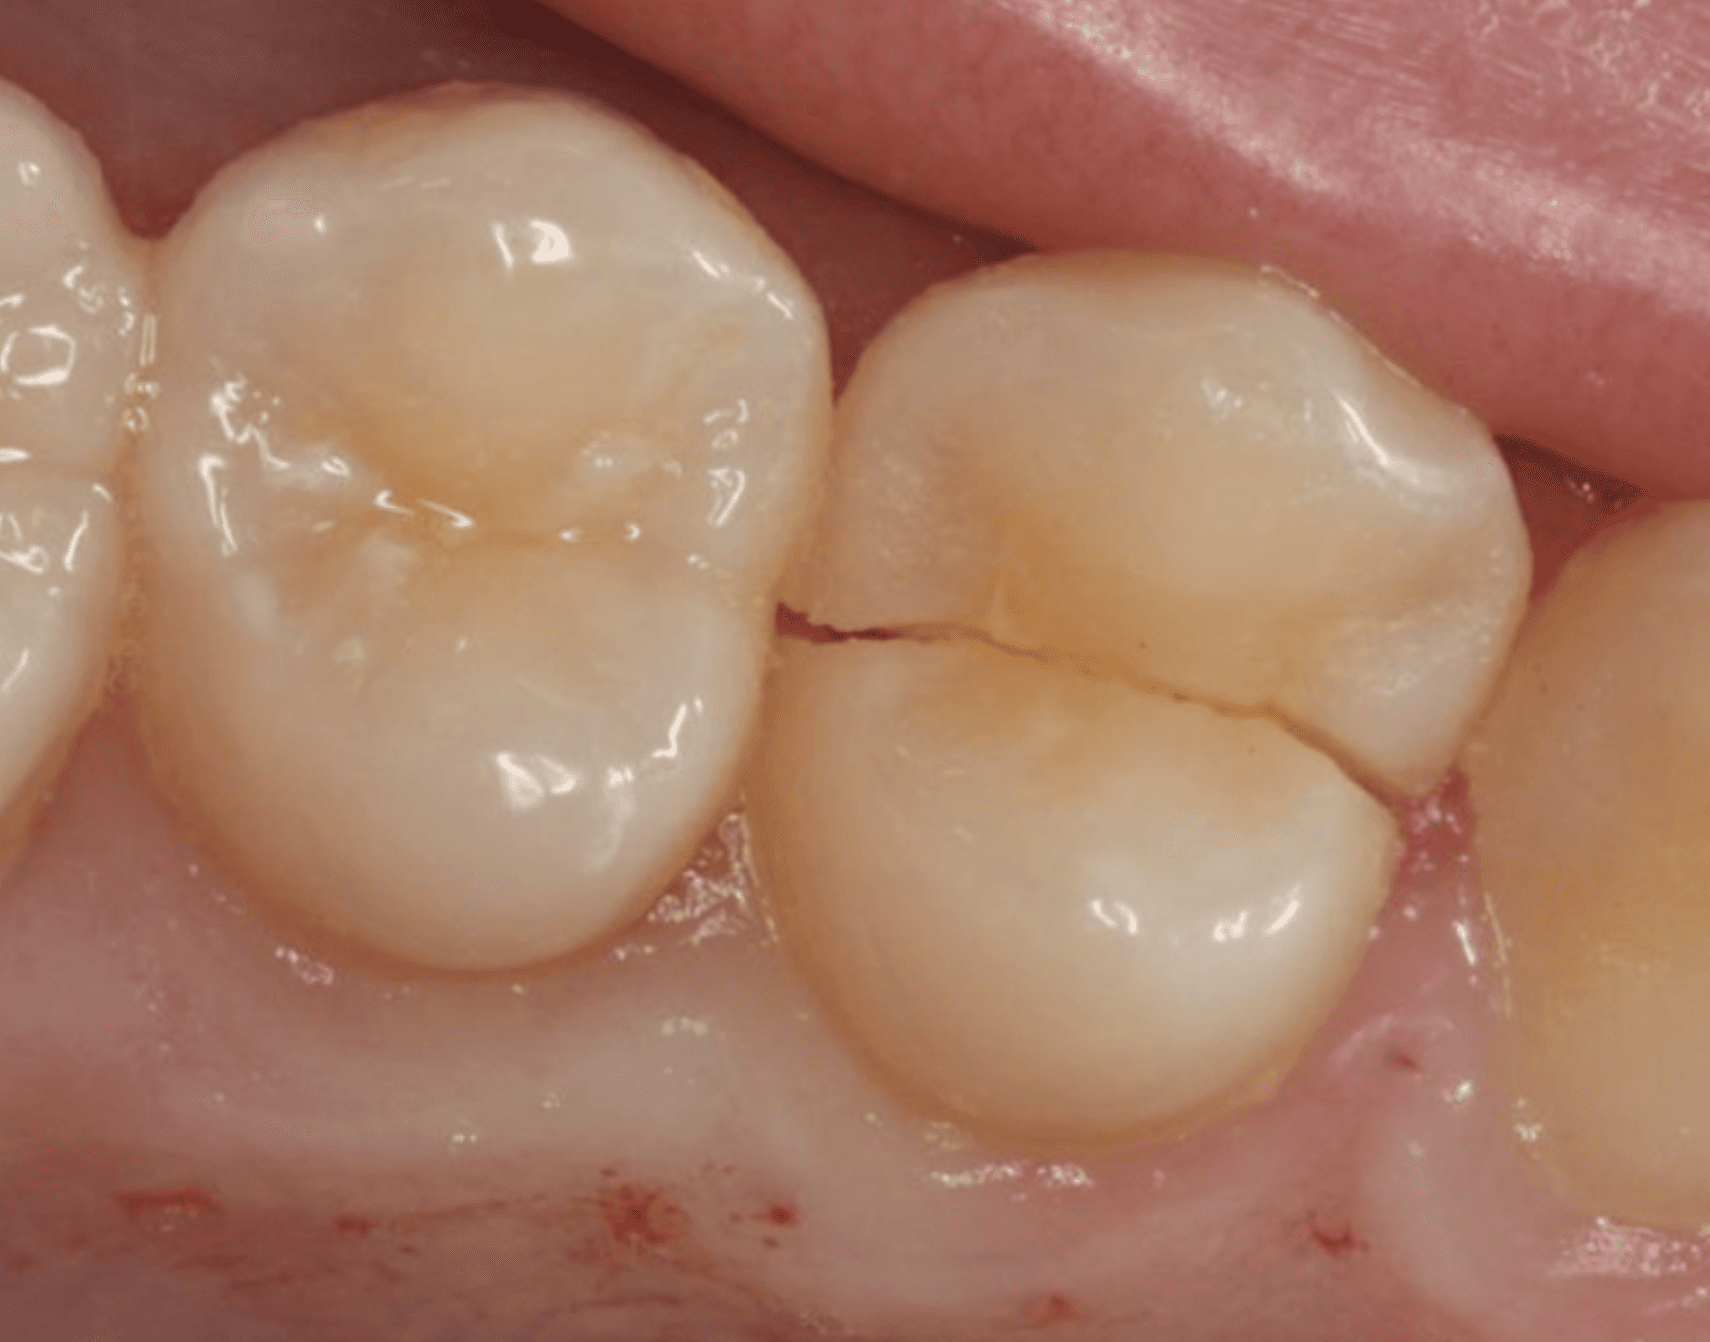

충치 치료

One Day 인레이 – 하루 만에 끝내는 충치 치료

충치 치료, 더 이상 미루거나 두려워하지 마세요.

직장‧학교‧가사로 바쁜 요즘, 2-3회 내원은 큰 부담이 됩니다.

플란트구강악안면외과 치과는 3D 디지털 스캔+설계+밀링 시스템으로 인레이 제작-부착을 당일에 완료해 시간을 확 줄였습니다.

빠르지만, 정밀합니다

정확한 디지털 스캔으로 치아 형태를 ㎛ 단위까지 캡처

CAD/CAM 설계로 틈새 없이 맞춤 제작

세라믹 블록을 밀링해 색·투명도까지 자연스럽게 구현

의사가 즉시 적합도·교합을 확인하니 추가 조정 필요 거의 없음

One Day 인레이의 핵심 장점

시간 절약 | 단 한 번 방문으로 치료·복귀

높은 내구성 | 디지털 설계-가공으로 강도·정밀도 향상

심미성 | 치아 색상과 자연스럽게 어우러져 앞니도 OK

편리한 예약 | 탄력 스케줄 운영, 퇴근 후·주말 진료 가능

충치 때문에 스케줄을 비우기 어렵다면 One Day 인레이로 하루 만에 해결하세요.

용현동 플란트구강악안면외과 치과가 빠르고 정밀한 디지털 치료로 당신의 시간을 지켜드립니다.